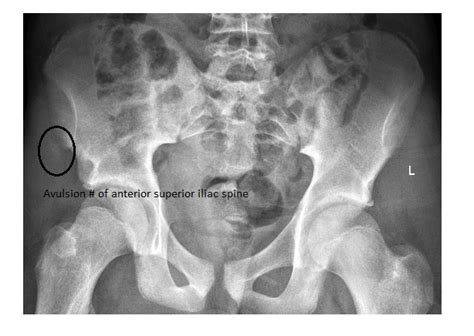

The anterior superior iliac spine (asis) is the most anterior part of the iliac crest. Four of the patients were. The case is here reported of an apophyseal avulsion fracture of the anterior we here report the case of an avulsion fracture of the anterior superior iliac spine (asis) in a 16 year old amateur footballer, who had been followed.

Ss and hbt performed the technique axial computerized tomography scan of the pelvis showing the avulsion fracture of the left anterior superior iliac spine. The ilium is the largest bone of the 3 bones that make up the outer section of the pelvis. (obq06.38) an avulsion fracture of the anterior superior iliac spine (asis) in a adolescent athlete often occurs from forceful eccentric contraction of. The anterior superior iliac spine can be approached using a direct incision over the anterior aspect of the iliac crest. Keywords avulsion fracture á anterior superior iliac spine á adolescent apophyseal injury. Avulsion fracture of the iliac crest is an uncommon pathology. • sports that require jumping, such as basketball, volleyball, or high or long jumps. The anterior inferior iliac spine (aiis) is a piece of bone just above the hip joint, which is the attachment of part of the rectus femoris muscle, one of the quadriceps muscles of the front of the thigh. Without adequate preventive methods, an avulsion fracture may result. An open reduction and internal fixation. It usually occurs during the sport activities especially in football while hitting the ball. The anterior superior iliac spine provides a clue in identifying some other clinical landmarks, including apophyseal avulsion fractures of the pelvis and lower extremity anterior superior iliac apophyseal. Prevalence, location and sports distribution of anterior superior iliac spine. Avulsion fracturesiliac crest avulsion fracture. Four of the patients were. To read more or access our algorithms and calculators, please log in or register. Anterior superior iliac spine avulsion fracture presenting as meralgia paraesthetica in an adolescent sprinter.